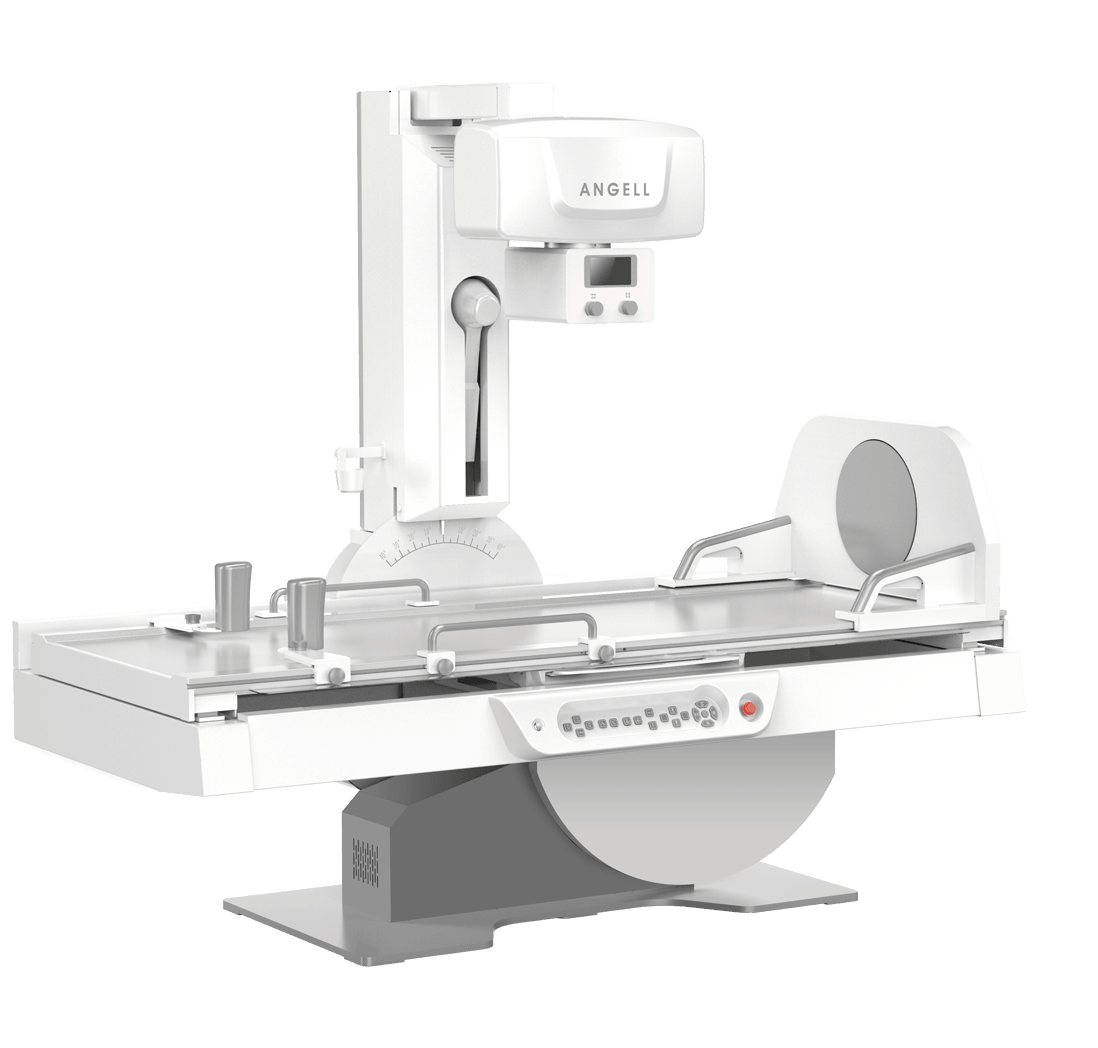

多功能診斷應用專業設計

從醫療機構放射科的實際應用出發,針對多功能診斷進行多維度專業設計,優化病人檢查體驗,大幅提升操作技師工作效率。

多功能+

多功能專用結構設計

輕松滿足各種角度投照及塵肺檢查需求 -

多功能+

超低床體設計

病人輕松上下床 -

多功能+

旋轉腳踏設計

醫生可輕松便捷遙控病人轉體,提升一倍查體效率 -

多功能+

一體化操控臺設計

集成化操控臺,支持系統一鍵開關機,支持醫生雙手協同操控 -

多功能+

可移除式濾線柵設計

有效滿足婦科兒科檢查時的低劑量要求 -

多功能+

升降型移動操控臺設計

升降式設計保障不同高度的操作舒適度,支持醫生進行床邊操控、曝光及觀察